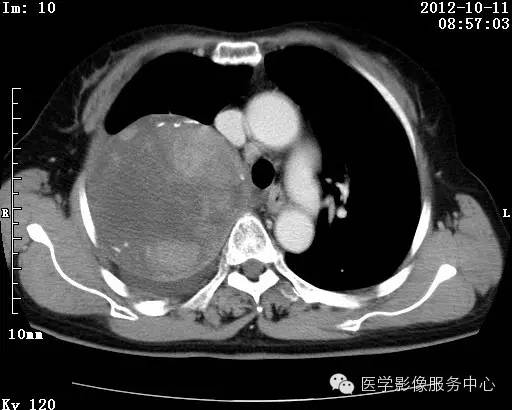

【病例】右肺巨大错构瘤1例CT影像表现

病史:女 65岁咳嗽咳痰 右肺巨大肿块就诊。

错构瘤的主要组织成分包括软骨、脂肪、平滑肌、腺体、上皮细胞,有时还有骨组织或钙化。错构瘤一般为实质致密的球形、卵圆形,也可以是分叶状或结节状,大多数直径在3cm以下。

错构瘤的发病年龄多数在40岁以上,男性多于女性。 绝大多数错构瘤(约80%以上)生长在肺的周边部,紧贴于肺的脏层胸膜之下,有时突出于肺表面。其特征钙化为爆米花样钙化,内有脂肪软骨成分等等。最常见的部位是胸膜下肺实质内,其次为主支气管或肺叶、肺段支气管内。

瘤内出现“爆米花样钙化”是诊断的主要指标之一。早期的点状、斑片状及结节状钙化 随时间增加钙化数量及范围会增加,最终可能演变 为爆米花样钙化;

另一项主要指标是瘤测得脂肪成分是诊断错构瘤。